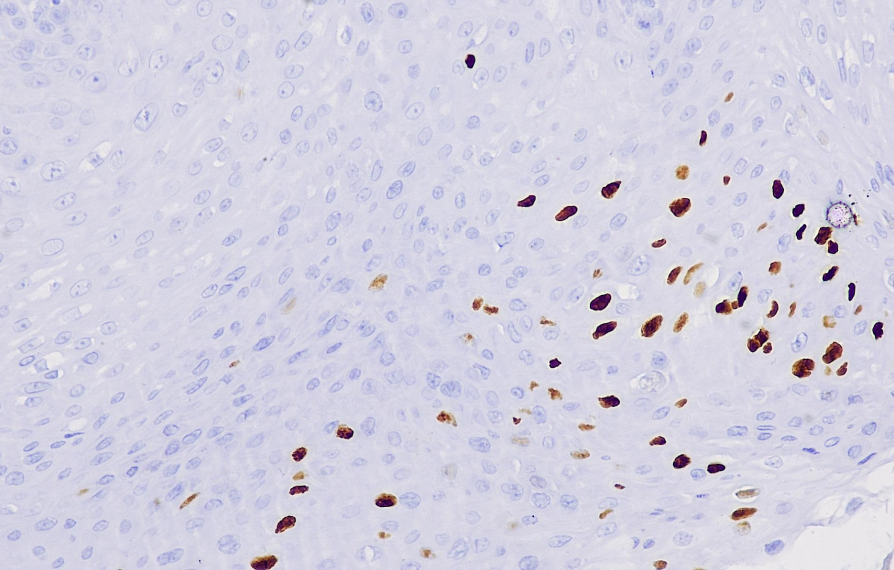

Positive control: HPV infected tissue

This antibody is a broad-spectrum HPV virus marker that can recognize HPV subtype antigens of 6, 11, 16, 18, 31, 33, 42, 51, 56 and 58 in human tissues. It is mainly used for the research of skin or mucosal lesions caused by HPV virus infection (such as condyloma acuminatum).

The Papilloma Virus antibody reagent can specifically bind to the Papilloma Virus molecular antigen. The immunohistochemical kit containing the Papilloma Virus antibody reagent is suitable for the auxiliary diagnosis of skin or mucosal lesions caused by HPV virus infection.